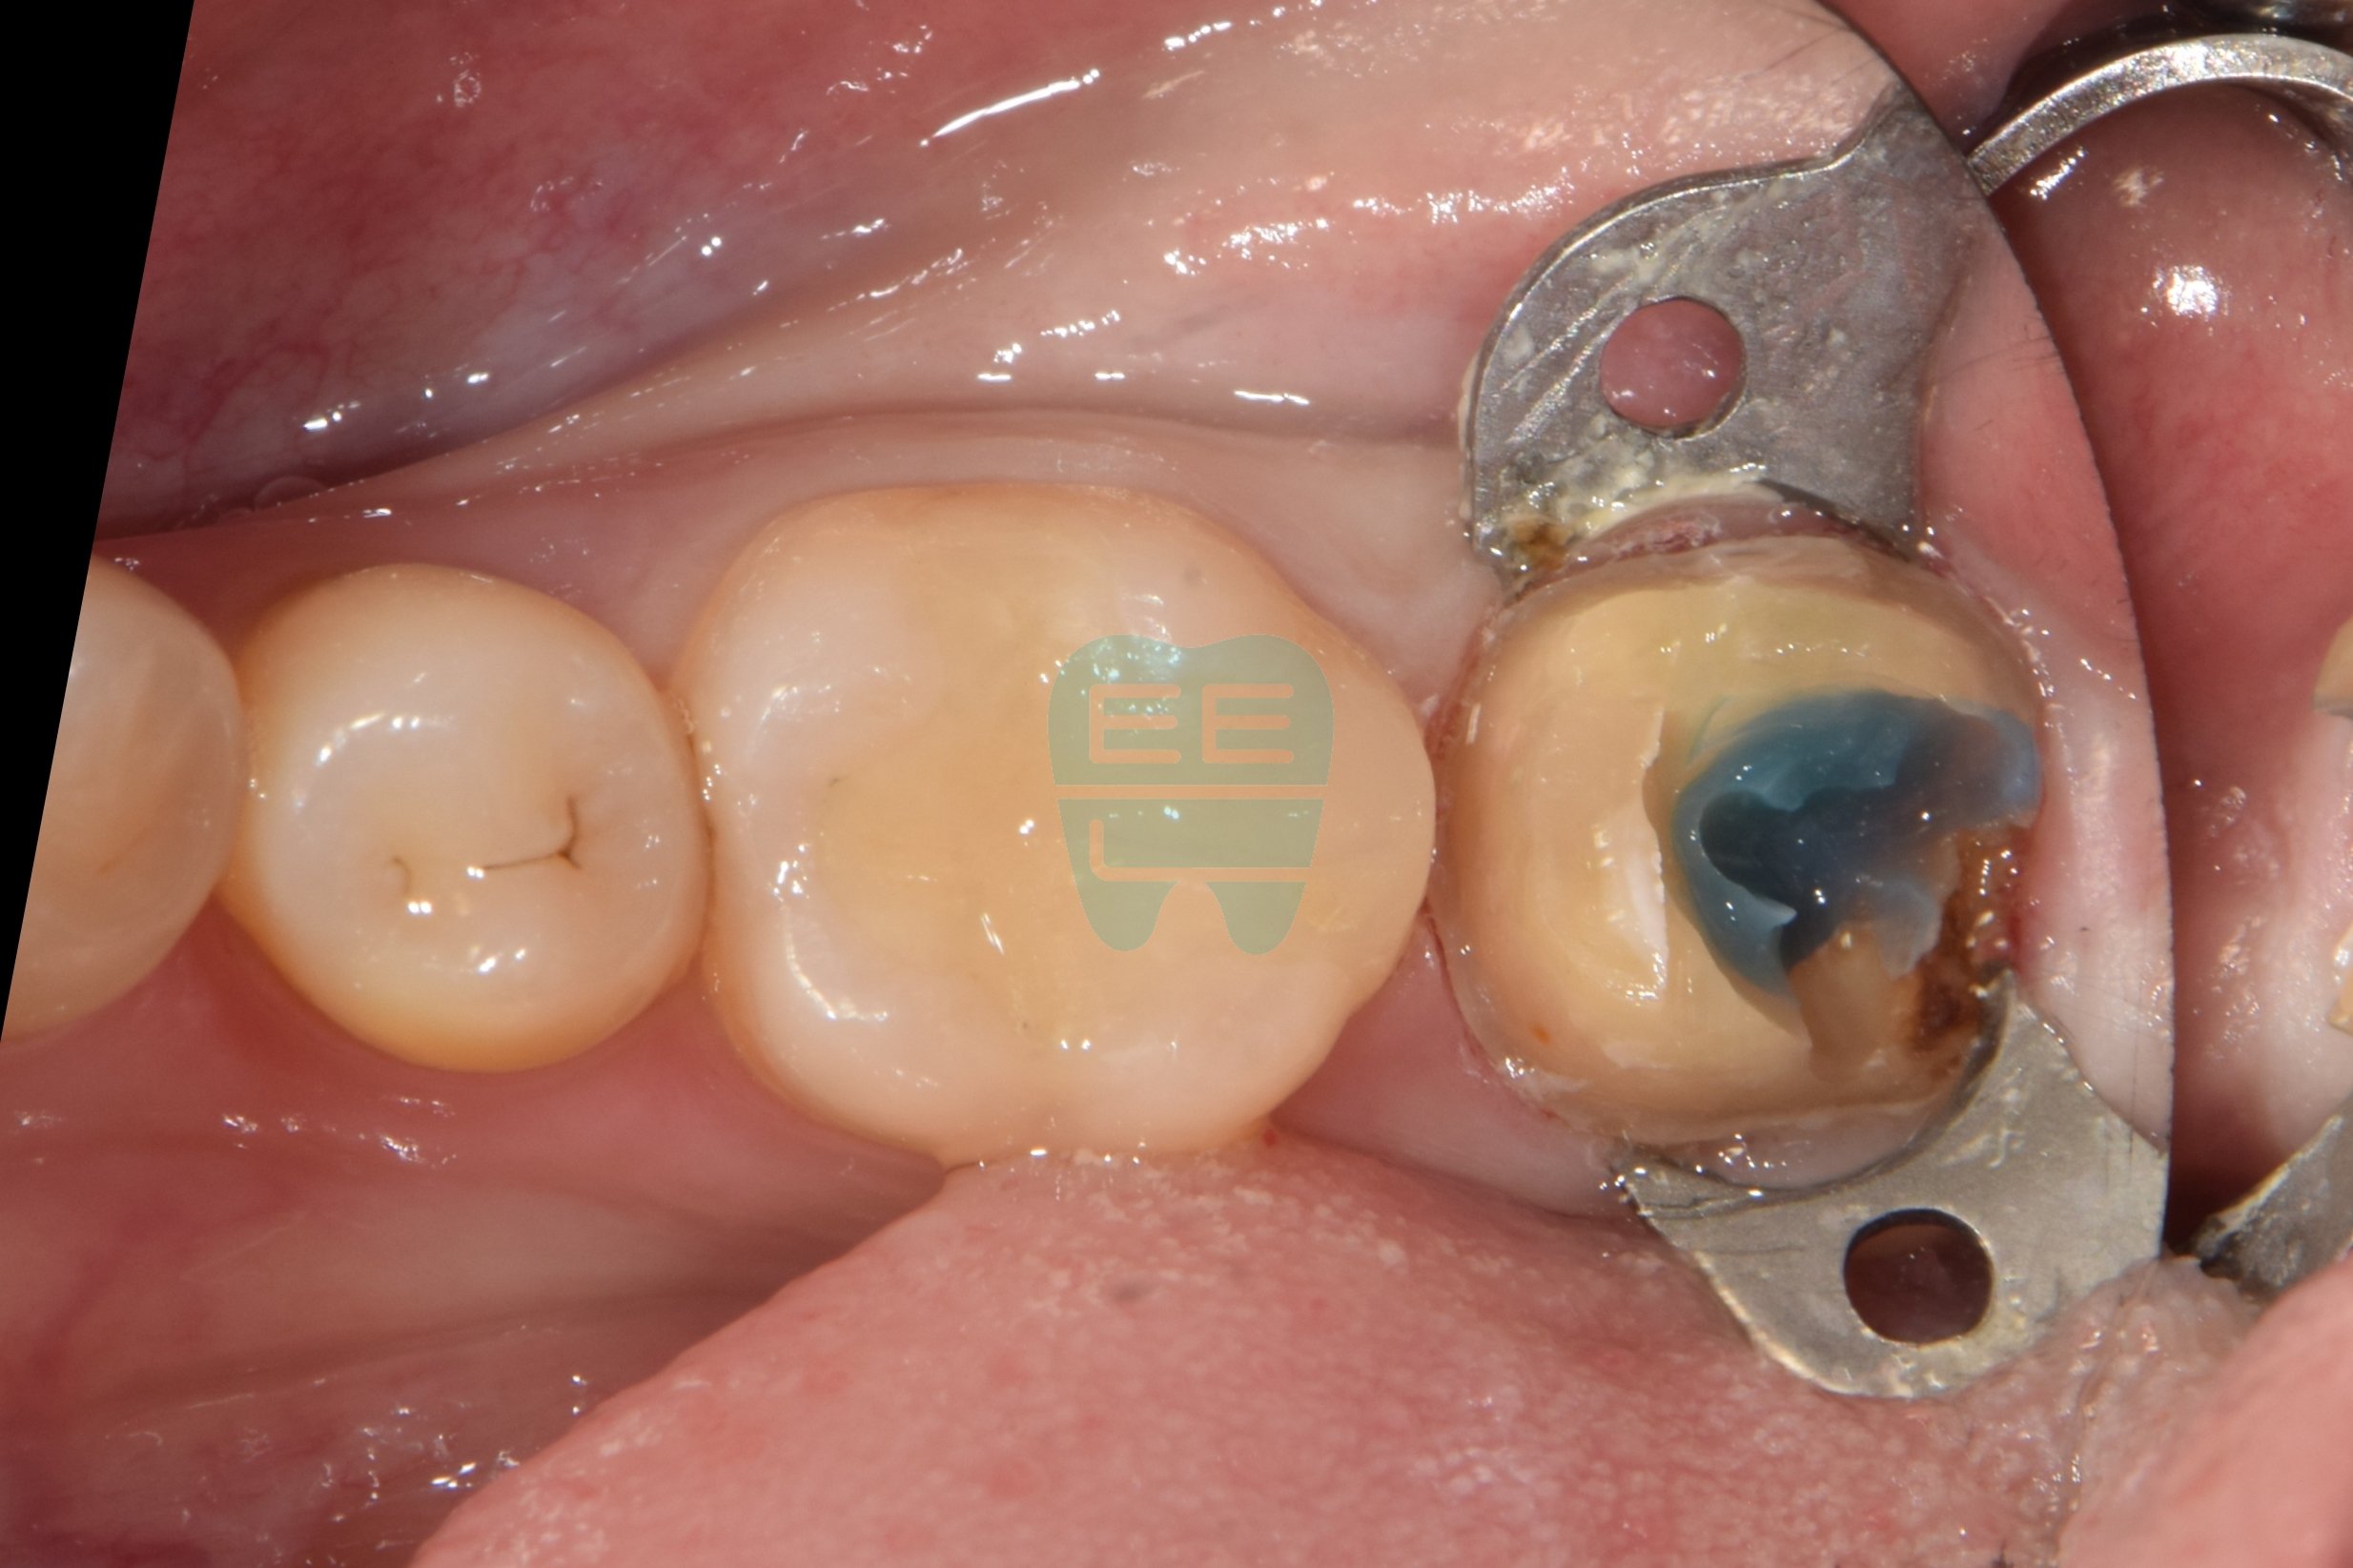

STEP 4. 러버댐 장착 및 Wall 쌓기

재근관치료의 성공률을 높이기 위한 가장 중요한 단계입니다. 먼저 러버댐(Rubber Dam)을 장착하여 타액과 세균을 완벽하게 차단합니다. 그리고 소실된 원심면 치아 벽을 레진으로 꼼꼼하게 쌓아 올려(Wall Build-up) 밀폐된 환경을 만듭니다.

이 'wall쌓기' 과정이 바로 오늘 치료의 핵심입니다. 많은 분들이 "그냥 빨리 신경치료하고 씌우면 되는 거 아닌가요?"라고 생각하시지만, 이 벽이 없으면 근관 치료 중 소독액이 새어나가고, 침이 들어와 세균 감염이 재발합니다. 처음 치료가 실패한 이유가 바로 이 과정의 부실함에 있는 경우가 많습니다.